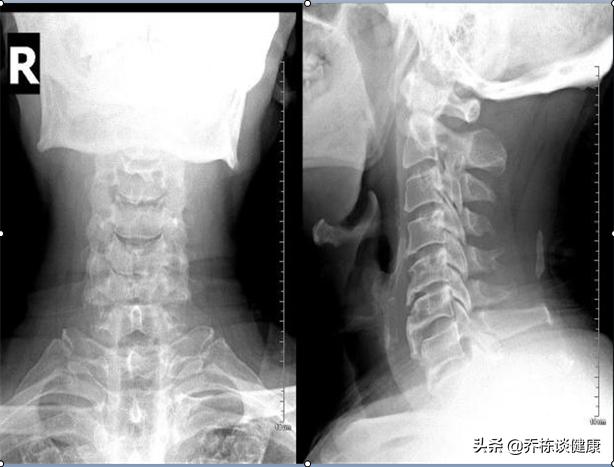

2.頸椎症によるめまい

椎骨動脈が頚椎の横孔を走行するため、主に椎骨動脈型頚椎症でみられる。 頚椎の安定性不良、骨棘、外傷などが原因で横孔に位置する椎骨動脈が圧迫され、椎骨動脈の一過性の血液供給不全が起こり、めまい、吐き気、嘔吐が突然発症し、頚部を動かしたときに多くみられる。

第二に、頸椎症患者の中には、主に頸部を動かしたときや朝に起こるエピソード性のめまいを呈することがある。

6、頚椎症

長時間の姿勢や寝姿勢が悪いと、頚椎の湾曲が変形し、頚椎の過形成、変形、変性、頚筋の硬化が起こり、頚部の血管が長時間圧迫され、動脈血の供給障害が起こり、脳への血液供給が不足すると、めまいの症状が現れます。